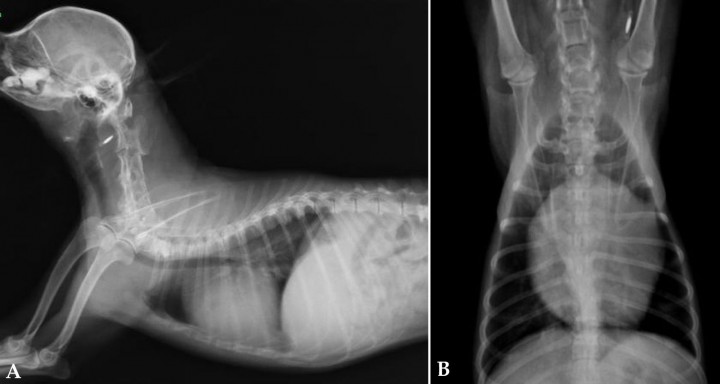

La radiografía es una de las primeras pruebas realizadas que nos harán tener una primera sospecha de neoplasia cardiaca. Observaremos signos de aumento de tamaño de la silueta cardiaca, siendo importante valorar la coexistencia de masas pulmonares.

Los hallazgos que podemos encontrar son:

- Aumento de tamaño de la aurícula izquierda (Fig. 2). La aurícula izquierda se sitúa ventral al bronquio principal izquierdo. En el aumento de tamaño de la aurícula izquierda observaremos una desviación dorsal del bronquio en la proyección lateral. En la imagen ventrodorsal veremos un aumento de separación entre los bronquios principales y una desviación hacia las dos de la orejuela izquierda.[ García MI: Atlas de interpretación radiográfica en pequeños animales. Zaragoza: Ed Servet; 2014. ]

<p>Radiografías de la cavidad torácica de un paciente con un tumor en la aurícula izquierda. (<strong>A</strong>) Lateral. (<strong>B</strong>) Ventrodorsal.</p>

Radiografías de la cavidad torácica de un paciente con un tumor en la aurícula izquierda. (A) Lateral. (B) Ventrodorsal.

- Aumento de tamaño del ventrículo izquierdo: suele producir un desplazamiento dorsal de la tráquea en la zona de la carina en la proyección lateral.

- Aumento de tamaño de la aurícula derecha (Fig. 3): produce un desplazamiento dorsal de la tráquea craneal a la carina sin afectar a esta en la proyección lateral.

<p>Radiografías de la cavidad torácica de un paciente con un tumor en la aurícula derecha. (<strong>A</strong>) Lateral. (<strong>B</strong>) Ventrodorsal.</p>

Radiografías de la cavidad torácica de un paciente con un tumor en la aurícula derecha. (A) Lateral. (B) Ventrodorsal.